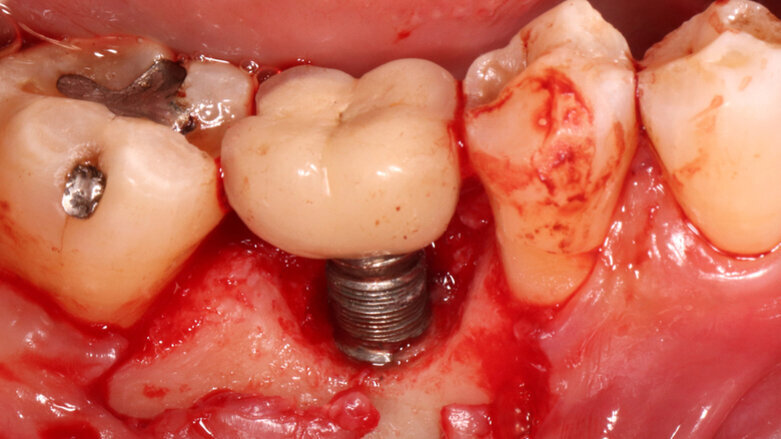

The researchers found that early implant failure is normally caused by the lack of attaining or maintaining osseointegration, or bone overheating or site contamination. Late implant failure is triggered by implant fractures, malpositioned implants and progressive peri-implantitis. The last causes 81.9% of late implant failures. Early implant failure results in implants that are normally mobile and easy to remove. Late implant failure means the implants can be at least partly osseointegrated and, therefore, more difficult to remove.

As options for implant removal, the study determined tooth extraction, trephine burs, piezo-surgery, laser surgery, the counter-torque ratchet technique (CTRT) and electrosurgery. Even though trephine burs seem to be the best-known method for implant removal, the CTRT method, alone or combined, should be the first choice for the clinician because of its low invasiveness.